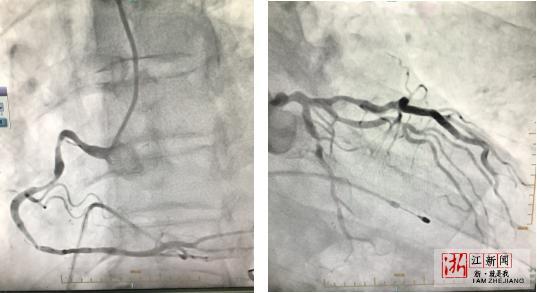

冠脈造影提示 冠脈嚴重病變

各類證據已經指向冠心病,為了進一步確診,老陳又接受了診斷冠心病的“金標准”——冠脈造影,結果提示,老陳的冠狀動脈有三支存在嚴重病變,其中一根血管99%堵塞。到此,老陳常年胸悶氣急的“元兇”終於浮出水面。

大隱靜脈橋遠端和近端吻合

按照術前手術方案,醫生在老陳左胸第4肋間切開一個7釐米直徑的小孔,在心髒不停跳下行乳內動脈和左前降支搭橋,同時取右下腿靜脈,同樣在心髒不停跳下搭右冠狀動脈,搭完兩支主要的冠脈後,缺血的心肌重新得到了血流和氧供,心髒跳動明顯加強。